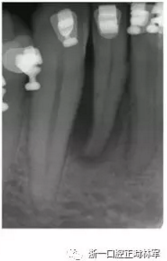

患者42-43區(qū)有復發(fā)性膿腫,42為兩壁骨袋,遠中牙周探診9mm(圖12),43探診提示有附著喪失但較穩(wěn)定。患者要求治療膿腫并排齊下頜牙列,因此決定通過拔除42解決擁擠。方案不采用GTR保留牙齒,通過正畸拔除42改造骨缺損形態(tài),獲得軟硬組織,避免拔牙區(qū)由于組織的萎縮出現(xiàn)不美觀的裂口。通過鄰牙的擠壓重建生理性鄰間解剖結構?;颊呤褂蒙鄠日辰?,初期通過牽引42,43以排齊并修復43近中骨缺損。隨后緩慢牽引42,42處加轉矩扭轉牙以增加頰側骨量并減少軟組織塌陷,避免后期拔牙由于骨皮質薄導致的裂縫,先用0.016TMA后用0.017×0.017帶鉤TMA完成(圖13-16)。